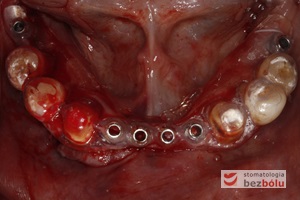

Wprowadzenie 4 implantów w odcinku przednim żuchwy